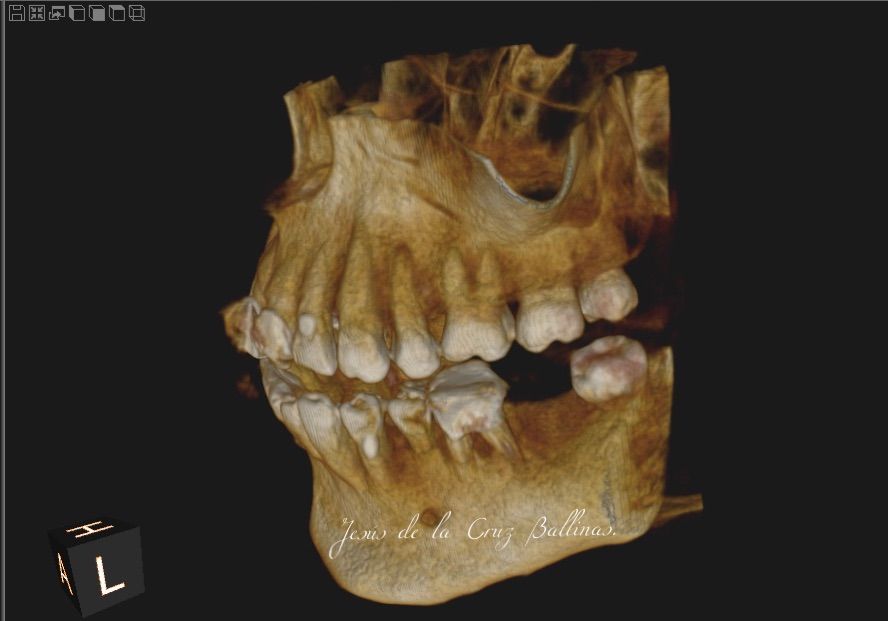

Especialista en Implantología Oral quirúrgica y protesica, cédula de especialidad: 12411844

La especialidad en Implantología Oral se enfoca en sustituir órganos dentarios perdidos por implantes dentales mediante una fase quirúrgica y una fase protesica y de esta manera devolver la función, estetica y confort dental del paciente.

Contamos con tecnología de punta que nos facilitara el diagnostico y tratamiento de tu problema dental lo cual hará mas predecible el éxito a largo plazo.